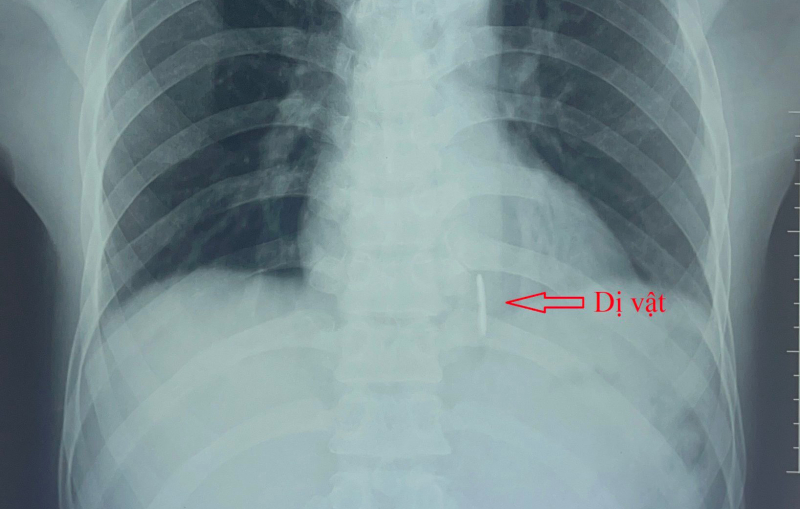

Kết quả X-quang tim, phổi thẳng; siêu âm tim màu; chụp cắt lớp vi tính lồng ngực... ghi nhận 1 dị vật cản quang dài 4cm đường kính 0,4cm nằm dọc thành sau thất trái thông vào buồng tim. Bệnh nhân được chỉ định phẫu thuật cấp cứu.